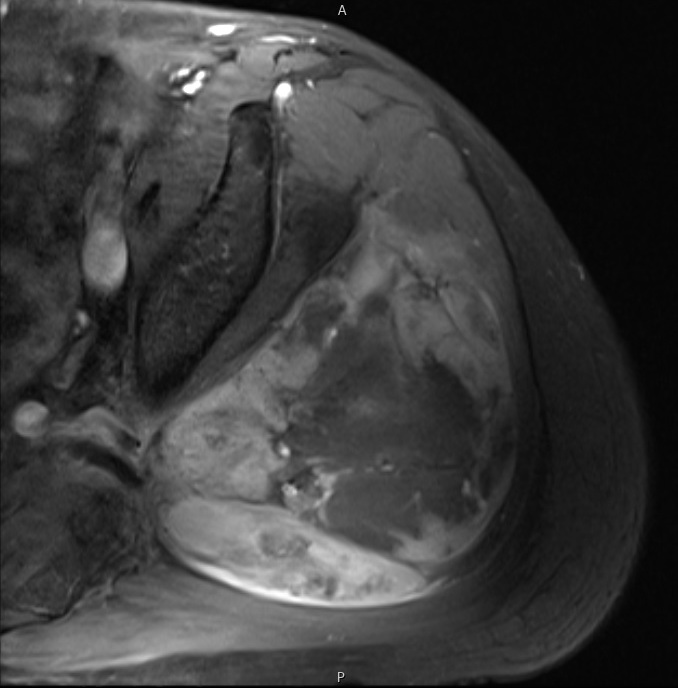

• Contrasted images show hyper-enhancement of the tumors. (Fig. 4, 5, 11-13)

Axial (Fig. 4) and Coronal (Fig. 5) contrasted T1-weighted MR images show a large heterogeneous mass with central and peripheral enhancement. Central low signal intensity image is compatible with necrosis and hemorrhage.